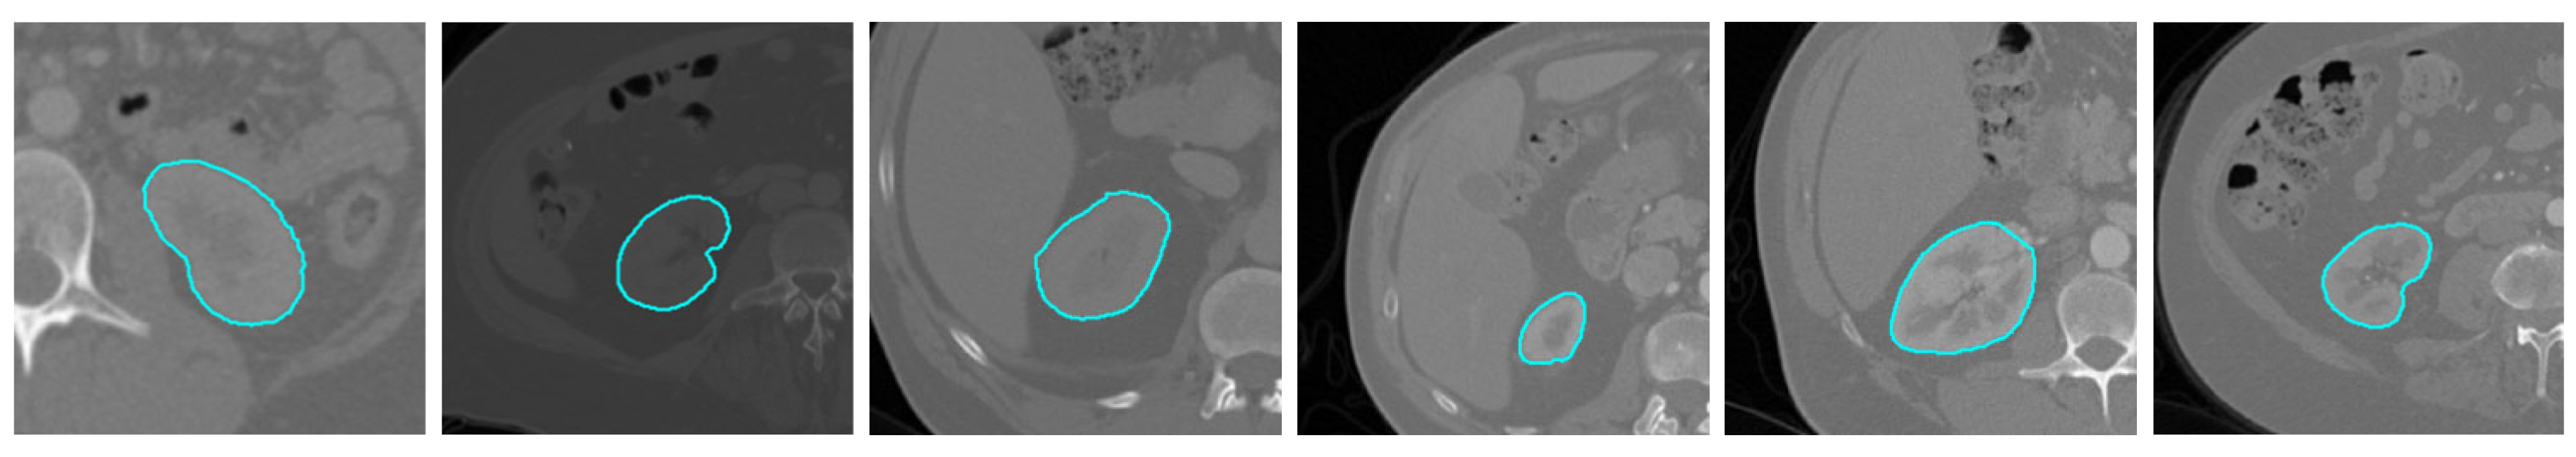

2.1. Data